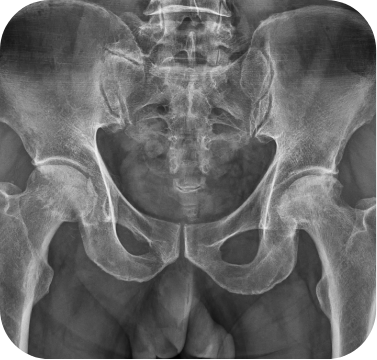

고관절 무혈성괴사 환자의 인공관절 전치환술 사례

• ▲ 수술 전

• ▲ 수술 후

고관절 퇴행성관절염 환자의 인공관절 전치환술 사례